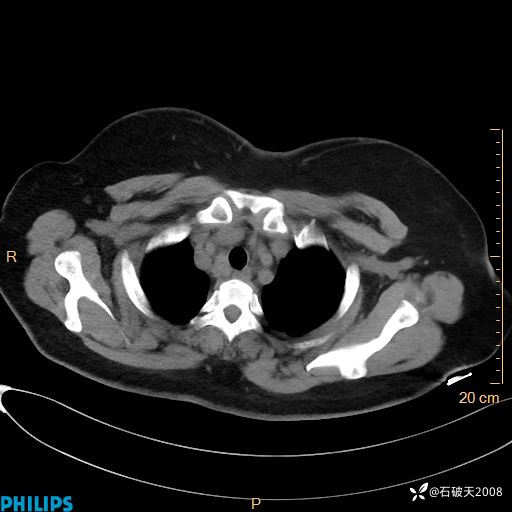

肺结节病?纵膈型肺癌?淋巴瘤?有点意思,欢迎围观

女 52岁 主 诉:咳嗽10余天,咳痰2天。

现病史:10余天前无明显诱因出现咳嗽,呈阵发性干咳,伴咽喉部发痒,无咽痛,无咳痰,无鼻塞、流涕、打喷嚏,无发热、畏寒、寒颤,无头痛、头晕,无胸闷、胸痛,无反酸、烧心,无腹痛、腹泻,无尿频、尿急,无皮疹等,在当地诊所求治,给予口服药物治疗(具体不详),病情无好转。遂在当地社区卫生服务中心开具口服药物治疗(具体不详),疗效欠佳。2天前出现咳痰,在我院门诊求治,行胸部CT提示肺部感染,建议住院,患者要求口服药物治疗,目前仍咳嗽、咳白色粘痰,白天量多,夜间自觉喉部喘鸣音,遂再次来院就诊,以“肺部感染”为诊断收入院。发病以来,神志清,精神可,饮食可,夜间睡眠差,大小便正常,近期体重无明显变化。

动脉期